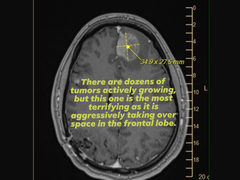

Na dowód załączyła również obraz skanu mózgu (MRI), który wykazał agresywny guz płata czołowego, błagając jednocześnie o wsparcie lub pomoc ze strony kierownictwa Epic Games, które podjęło kluczowe decyzje dotyczące zwolnień.